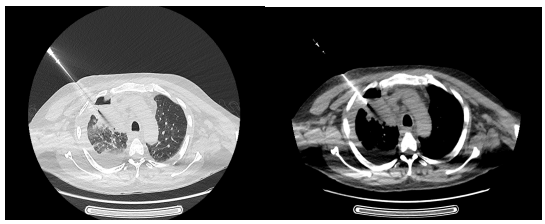

为确保手术的成功与安全,阿坝州人民医院运用多学科协作优势。外二科杜刚主任医师制定了详细的术中、术后并发症处理预案,为手术的成功提供了坚实的保障。放射科蒲鹏主任医师用经验和技术,为手术制定了精确的穿刺进针路线。在唐大东主任医师的精细操作下,整个穿刺过程仅用了约30分钟便顺利完成,且患者未出现明显的出血、气胸等并发症。

在穿刺过程中,医生们通过实时监测CT影像,不断调整穿刺针的位置和角度,以确保穿刺的准确性和安全性。